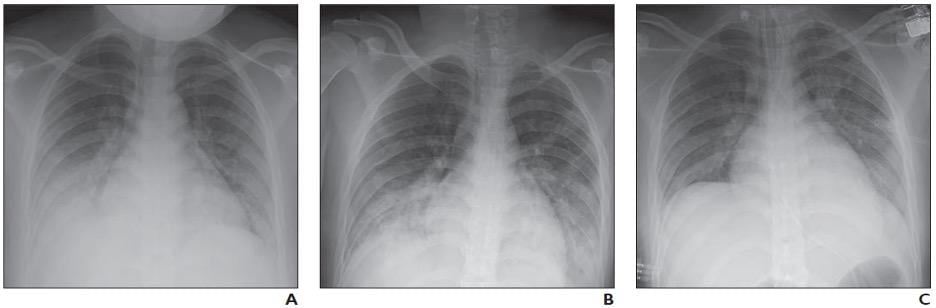

16-year-old girl with coronavirus disease (COVID-19) and known history of tuberous sclerosis who presented with acute hypoxic respiratory distress. Reverse transcription–polymerase chain reaction testing confirmed diagnosis of severe acute respiratory syndrome coronavirus 2 (SARS-CoV-2).

A, Frontal chest radiograph obtained at initial presentation shows bilateral lower lung zone–predominant consolidations and, to lesser extent, ground-glass opacities. B, Frontal chest radiograph obtained 2 days after hospital admission shows interval increase in consolidation in bilateral lower lung zones. C, Frontal chest radiograph obtained 6 days after hospital admission and treatment shows interval improvement in consolidations in bilateral lower lung zones.

Regarding the limited studies of pediatric patients with COVID-19, Foust et al. noted chest radiography “may show normal findings; patchy bilateral ground-glass opacity (GGO), consolidation, or both; peripheral and lower lung zone predominance.”